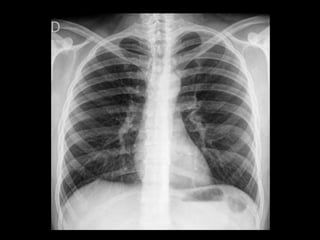

Rx. Tórax!!

• Rx tórax: